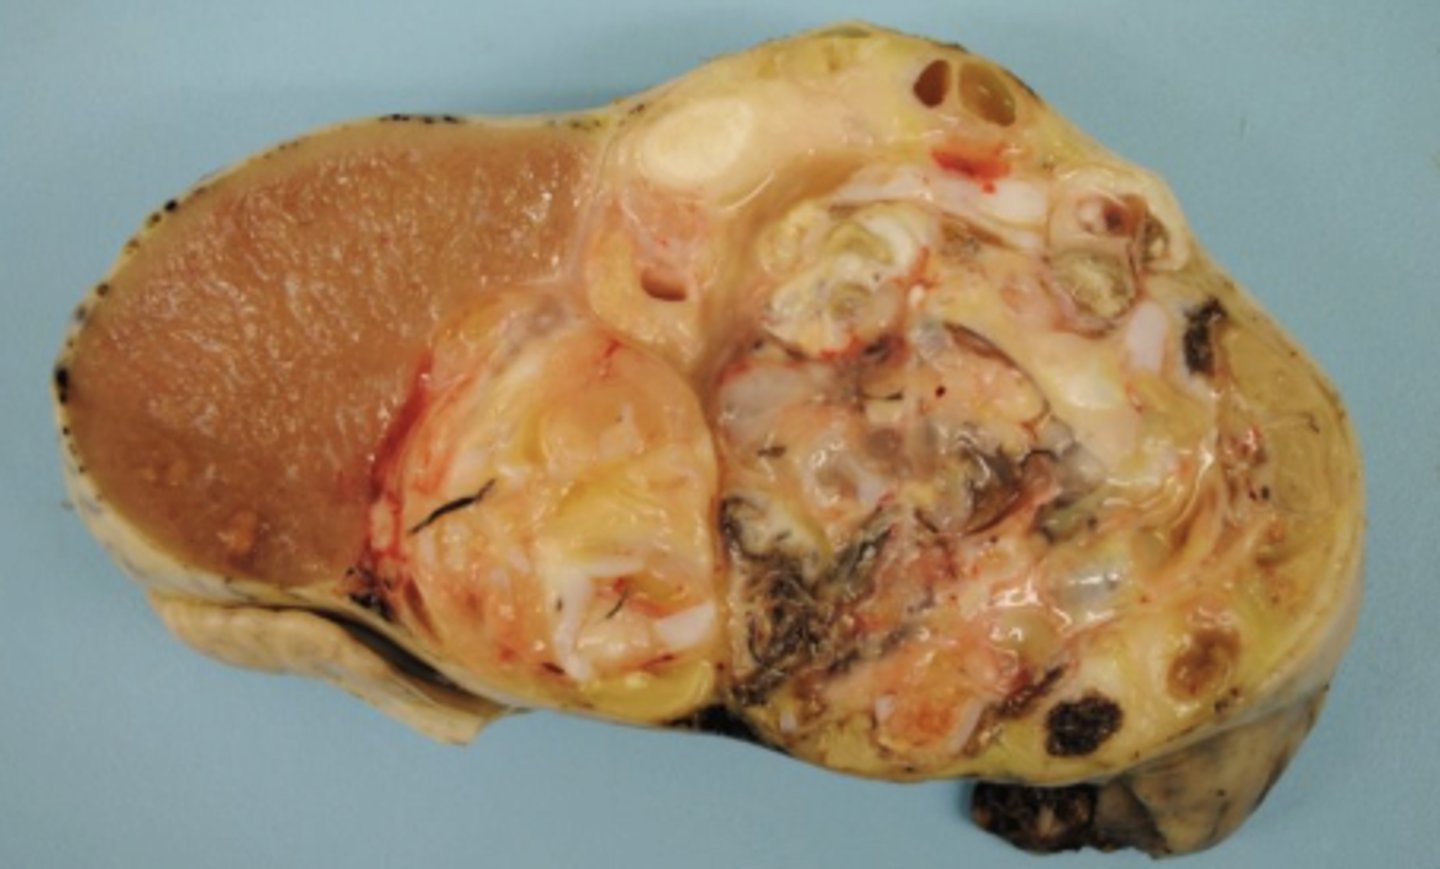

Mixed tumor

What kind of tumor is this?

Mixed tumor

-arise from totipotent germ cells

-can differentiate into variety of mature cell types

What kind of tumor is this?